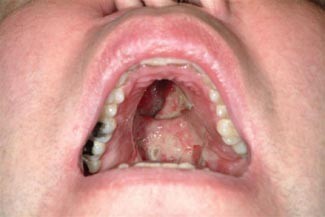

Palatal Perforation

Sometime after the nasal septum is perforated, the damage can turn downwards and open up a hole in the top of the mouth that slowly expands. This can limit your ability to speak clearly, eat, and swallow.

At this point, some choose to use wads of tissue paper or chewing gum (“cocaine gum”) to fill the open gap in their palate, between their nose and their mouth.

While it is possible for medical professionals to make a device to fill this gap, it’s not recommended except after long-term sobriety. As long as cocaine is still used, the perforation will continue to change and expand.